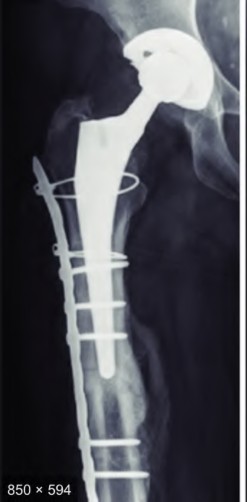

A 72-year-old female presents with progressive left thigh and knee pain for the last year. 5 years ago she sustained a femoral neck fracture treated with the implant seen in Figures A-C (current radiographs). The thigh pain is worse with weight-bearing. C-reactive

protein and erythrocyte sedimentation levels are within defined limits. Which of the following is the most likely cause of her pain?